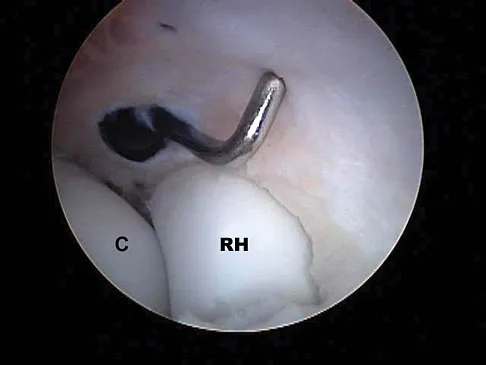

A football player sustains a traumatic anterior inferior dislocation of the shoulder in the last game of the season. It is reduced 20 minutes later in the locker room. The patient is neurologically intact and has regained motion. If the patient undergoes arthroscopic evaluation, what finding is seen most consistently?

Explanation